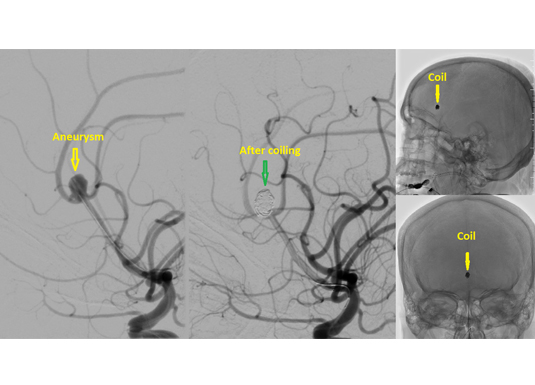

The arteries to brain may become like a balloon and burst inside the head. Such patient experiences the worst headache of their life. The balloon is called as an aneurysm. This condition is potentially fatal and has to be treated by embolization. We enter the aneurysm from the inside and fill it with coils. Blood does not enter the aneurysm after coiling and thereby eliminates the risk of the aneurysm bursting.